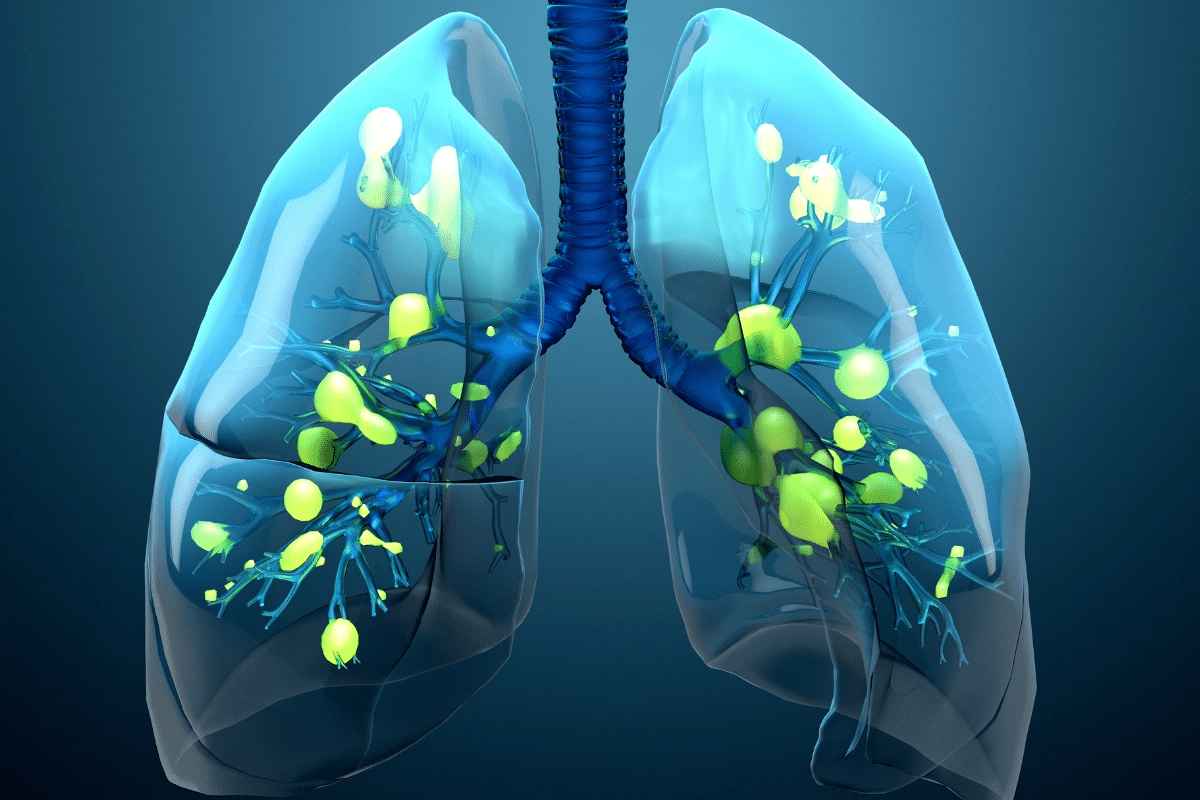

Pneumonia and COPD are closely linked in respiratory health. COPD makes it hard to breathe, while pneumonia is an infection that inflames the lungs. Both conditions can make each other worse.

Defining Both Respiratory Conditions

COPD, or chronic obstructive pulmonary disease, is a lung disease that gets worse over time. It’s mainly caused by smoking, but also by the environment and genetics. Pneumonia is an infection that inflames the lungs’ air sacs, filling them with fluid.

Adults 65 or older with COPD are 7.7 times more likely to get pneumonia than healthy people. COPD is common in those hospitalized with pneumonia, happening in 30% of cases. This makes managing both conditions harder, as COPD can make pneumonia worse.

How COPD Increases Pneumonia Susceptibility

People with chronic obstructive pulmonary disease (COPD) are more likely to get pneumonia. This is because their lungs can’t fight off infections well. We’ll look at how COPD affects the lungs and raises the risk of pneumonia.

Statistical Risk Analysis

Studies show that COPD patients are almost twice as likely to get pneumonia as the general public. This big difference shows why COPD patients need to watch their health closely. They should take steps to prevent pneumonia.

The table shows how much more likely COPD patients are to get pneumonia. It highlights their increased risk.

Physiological Mechanisms Behind Increased Risk

COPD patients’ lung function is not as good, making them more open to infections like pneumonia. Several reasons explain why they are more at risk:

- Impaired Mucociliary Clearance: COPD damages the cilia in the airways. This makes it harder for mucus and pathogens to be cleared.

- Increased Inflammation: COPD causes chronic inflammation. This makes it harder for the lungs to recover from infections.

- Weakened Immune Response: The lungs of COPD patients can’t fight off infections as well.

Knowing these reasons is key to finding ways to prevent and treat pneumonia in COPD patients.